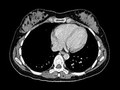

[ESOC2015]越来越多的证据支持为极重度卒中患者进行溶栓

一项大型脑卒中溶栓国际注册登记研究的新数据显示,组织型纤溶酶原激活物(tPA,阿替普酶)可安全用于极重度脑卒中患者的溶栓治疗。该研究的主要作者、来